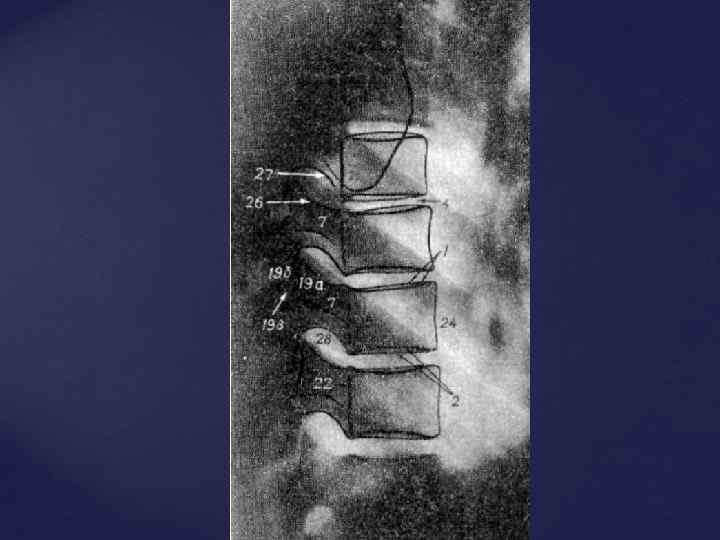

СРОКИ ОКОСТЕНЕНИЯ КОСТЕЙ ЧЕЛОВЕКА 1. ПОЗВОНОЧНИК - появление трех точек окостенения (т. о. ) (тело и две половины дуги) - внутриутробно - синостоз дуги и тела – 2 -3 года - синостоз обеих половин дуг – 1 -8 лет (в зависимости от уровня) - появление добавочных т. о. (апофизы - лимбы позвонков) – 7 -8 лет - полное слияние всех добавочных т. о. - 23 -26 лет - синостозирование крестца – 11 -12 лет

СРОКИ ОКОСТЕНЕНИЯ КОСТЕЙ ЧЕЛОВЕКА 1. ПОЗВОНОЧНИК - появление трех точек окостенения (т. о. ) (тело и две половины дуги) - внутриутробно - синостоз дуги и тела – 2 -3 года - синостоз обеих половин дуг – 1 -8 лет (в зависимости от уровня) - появление добавочных т. о. (апофизы - лимбы позвонков) – 7 -8 лет - полное слияние всех добавочных т. о. - 23 -26 лет - синостозирование крестца – 11 -12 лет